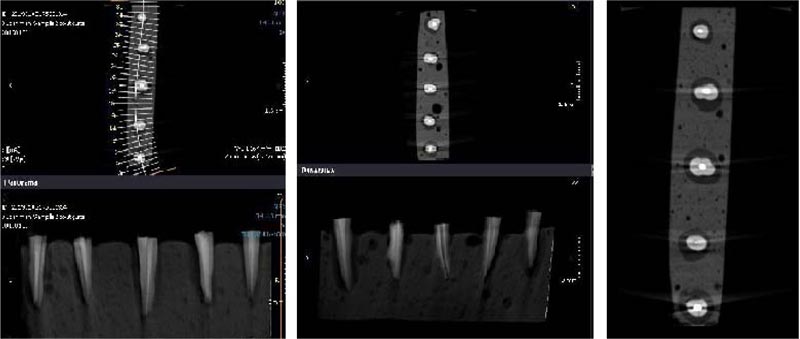

The apex of the prepared teeth was inserted into the wax, and then the teeth were placed in acrylic blocks (1 * 10 cm). A Cranex 3D CBCT device (Soredex, Tuusula, Finland) with 200 µm voxel size and 6 × 8 cm2 field of view (FOV) was used for scanning root fractures. Device settings were set to Kvp: 90, mA: 10, and time: 12 s. The images were then saved in DICOM format and evaluated using Ondemand 3D dental (Cybermed, Seoul, South Korea) software (Figs. 2 and 3). A 15-inch liquid crystal display monitor (Toshiba Satellite L40, Tokyo, Japan) with a 768 * 1367 pixel matrix was used for observation and interpretation of images in a dimly lit room with no time restriction. The images were assessed twice by an expert oral and maxillofacial radiologist and a dentist separately in two weeks. The two observers were allowed to adjust the brightness, contrast, and magnification of images to obtain the best visual results. All cross-sectional slices had 1-mm intervals and 0.5-mm thickness. Coronal, sagittal, and axial sections were used to detect VRF.